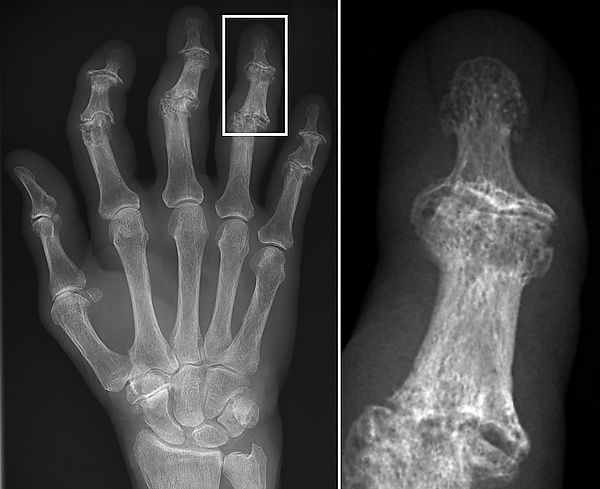

Остеоартрит — дегенеративное заболевание суставов, поражающее сочленения сочленяющихся элементов, или синовиальные суставы (например, коленные, плечевые), и характеризующееся повреждением хряща. Остеоартрит является наиболее часто регистрируемой патологией, обнаруженной в археологических человеческих останках, и широко используется в качестве маркера активности, отражающего связанные со стрессом модели деятельности или род занятий[6]. На его проявление также влияют такие факторы, как возраст, пол, размер тела и другие[7].

Кэтрин Марклейн из Университета штата Огайо изучила распространённость остеоартрита среди двух скелетных коллекций римского периода (II—III вв. н. э.), извлечённых из массовых захоронений в Оймаагаче, Везиркёпрю, Турция. Ранее с помощью анализа неметрических признаков было установлено, что несколько индивидов из одного из массовых захоронений демонстрируют биологическое родство друг с другом. Чтобы разработать подход к оценке возможного генетического и социально-исторического контекста, коррелирующего с остеоартритом, Марклейн поставил перед собой цель проверить, может ли сравнение различных моделей распределения мезаболевания жду семейными и несемейными группами указывать на семейное родство в Оймаагаче. Для исследования были отобраны десять синовиальных суставов у взрослых из участков 1 (17 человек) и 2 (23 человека). Исследование не выявило значимых данных, указывающих на корреляцию между остеоартритом и различными группами захоронения, а также на корреляцию между остеоартритом и биологически родственными лицами[8].